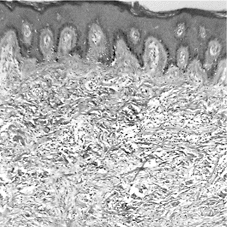

図2 隆起性皮膚線維肉腫の組織

H・E染色紡錘形細胞束は不規則に交錯を示し、

低分化な腫瘍細胞が増殖している。

本症例(図2)の光顕的所見は、皮下の基底部は境界明瞭で、その基底部下層に腫瘍を認める。線維芽部細胞の増殖が強く、核の多形成および核分裂像の増加がみられる。また、紡錘形細胞束は不規則に交錯を示し、膠原線維束間に低分化な腫瘍細胞が増殖している。組織学的に鑑別すべきものとして悪性神経鞘腫、悪性線維性組織球腫、滑膜肉腫があげられる。